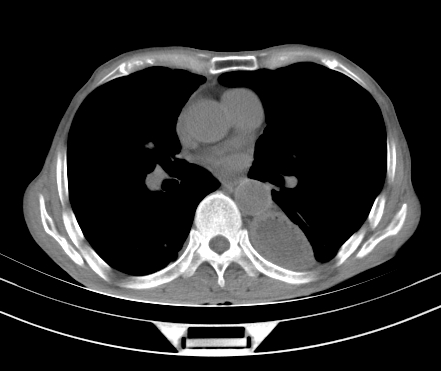

以下是引用gaoshengjiang在2008-5-30 19:53:00的发言:[br]右上叶可见大片实变影,其内可见充气支气管影及囊状影,右上叶尖端支气管走形区可见结节样影,左侧胸腔内可见胸腔胃影。纵隔淋巴结肿大。[br]考虑:1.右上肺阻塞性肺炎伴肺脓肿形成。支持转移所致。[br] 2.左侧胸腔胃。